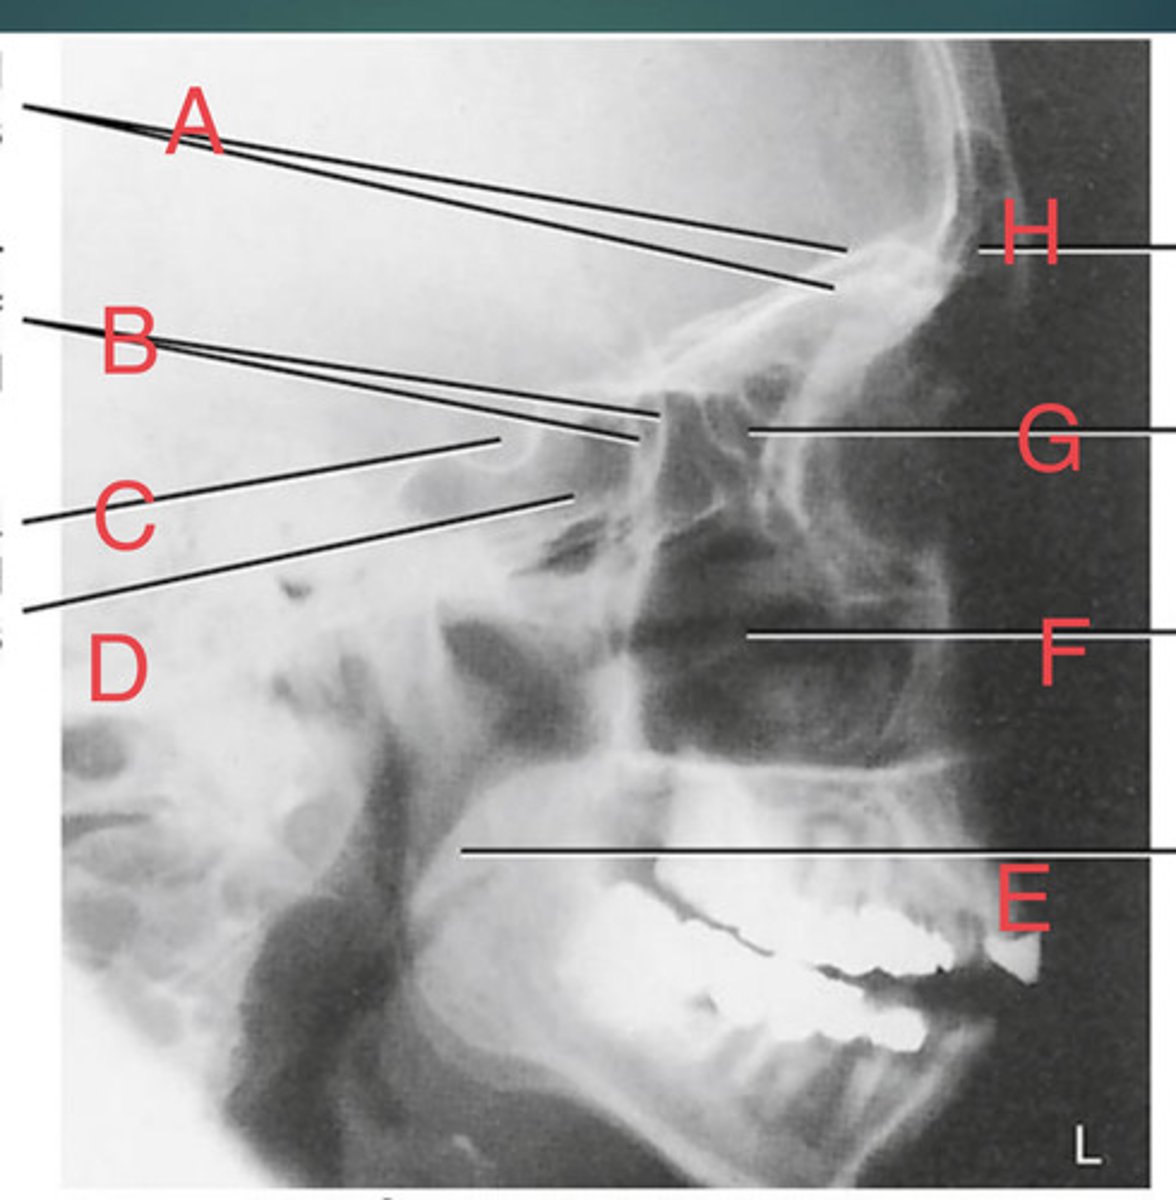

Lateral sinus

What position?

L. Orbital roofs

A.

L. Greater wings of sphenoid

B.

sella turcica of sphenoid

C.

L. Sphenoid sinus

D.

L. Rami of mandible

E.

L. Maxillary sinuses

F.

L. Ethmoid sinuses

G.

L. Frontal sinuses of frontal bone

H.